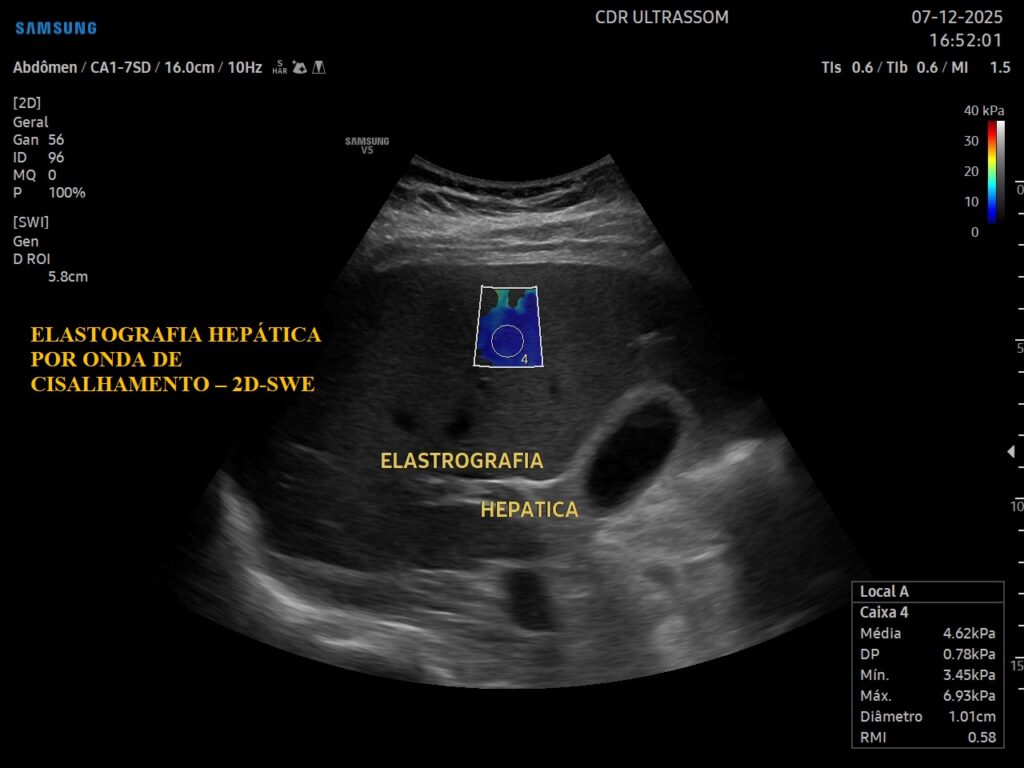

A elastografia mede a rigidez do tecido hepático, auxiliando na identificação e no estadiamento da fibrose sem necessidade de biópsia.

Contribui para a identificação de pacientes com risco de progressão para cirrose antes do surgimento de sintomas clínicos.

Permite o acompanhamento contínuo e seguro da progressão ou regressão da fibrose e da esteatose hepática.